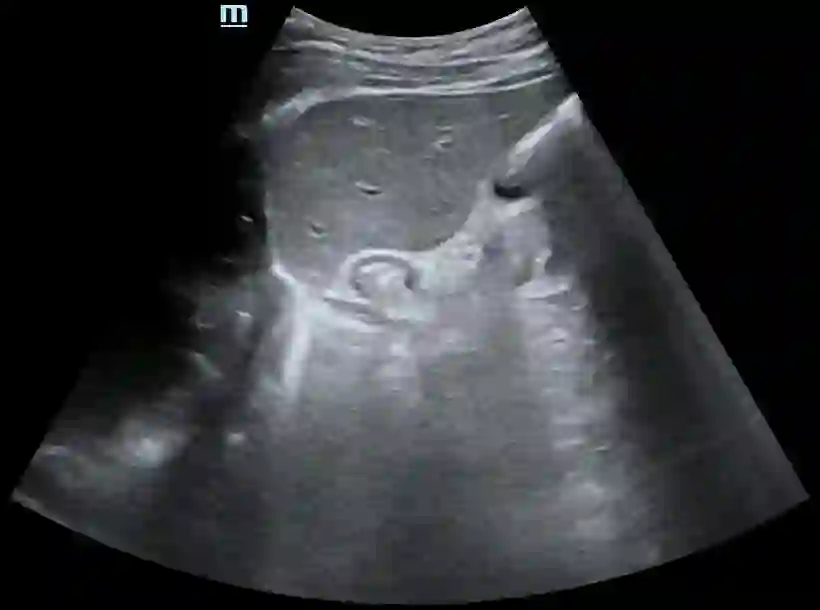

Most deep neural networks (DNNs) based ultrasound (US) medical image analysis models use pretrained backbones (e.g., ImageNet) for better model generalization. However, the domain gap between natural and medical images causes an inevitable performance bottleneck. To alleviate this problem, an US dataset named US-4 is constructed for direct pretraining on the same domain. It contains over 23,000 images from four US video sub-datasets. To learn robust features from US-4, we propose an US semi-supervised contrastive learning method, named USCL, for pretraining. In order to avoid high similarities between negative pairs as well as mine abundant visual features from limited US videos, USCL adopts a sample pair generation method to enrich the feature involved in a single step of contrastive optimization. Extensive experiments on several downstream tasks show the superiority of USCL pretraining against ImageNet pretraining and other state-of-the-art (SOTA) pretraining approaches. In particular, USCL pretrained backbone achieves fine-tuning accuracy of over 94% on POCUS dataset, which is 10% higher than 84% of the ImageNet pretrained model. The source codes of this work are available at https://github.com/983632847/USCL.